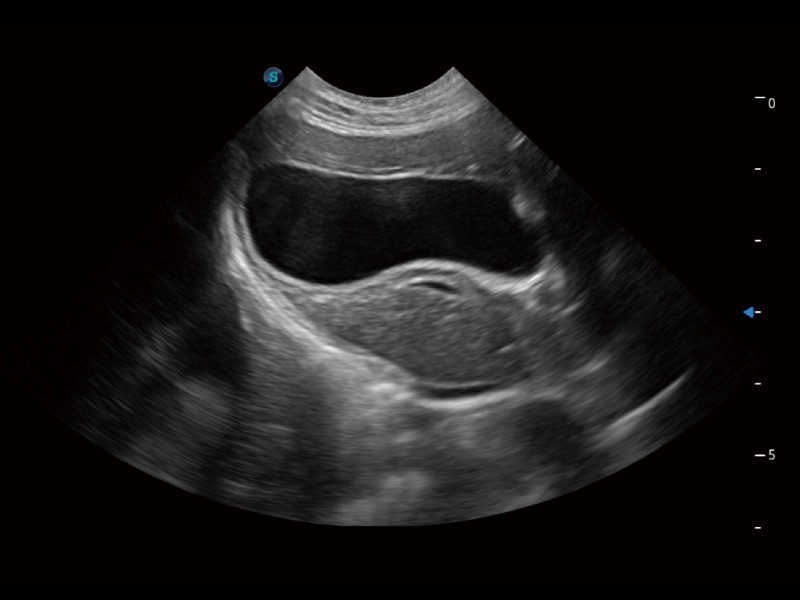

ProPet 70 进一步提升了微米成像算法,更加注重对基础原始图像的还原和保留,在有效减少斑点噪声、增强组织边界显示的同时,避免过度优化丟失真实的解剖信息。

一键自动识别膀胱壁及自动测量膀胱容积,不受膀胱形状和大小的限制,帮助医生快速精准获得测量的数据。